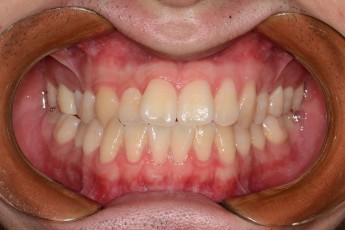

Before & After

Before

After